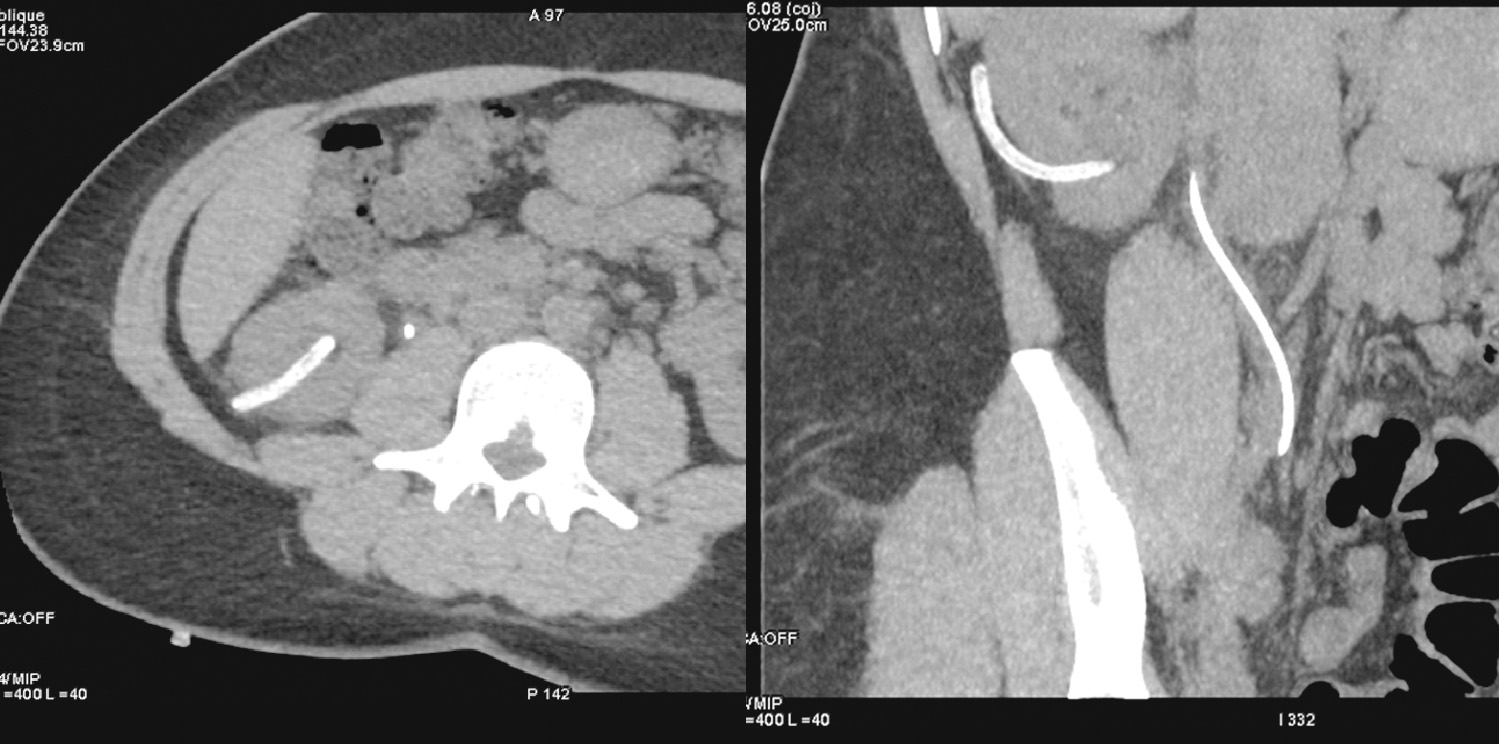

На следующие сутки после проведения литотрипсии для выявления остаточных конкрементов и контроля отсутствия осложнений выполнялась контрольная компьютерная томография (рисунок 4).

Рисунок 4. Контрольная КТ: в чашечно-лоханочной системе (ЧЛС) правой почки определяется контрольный дренаж и стент, конкремент не определяется.